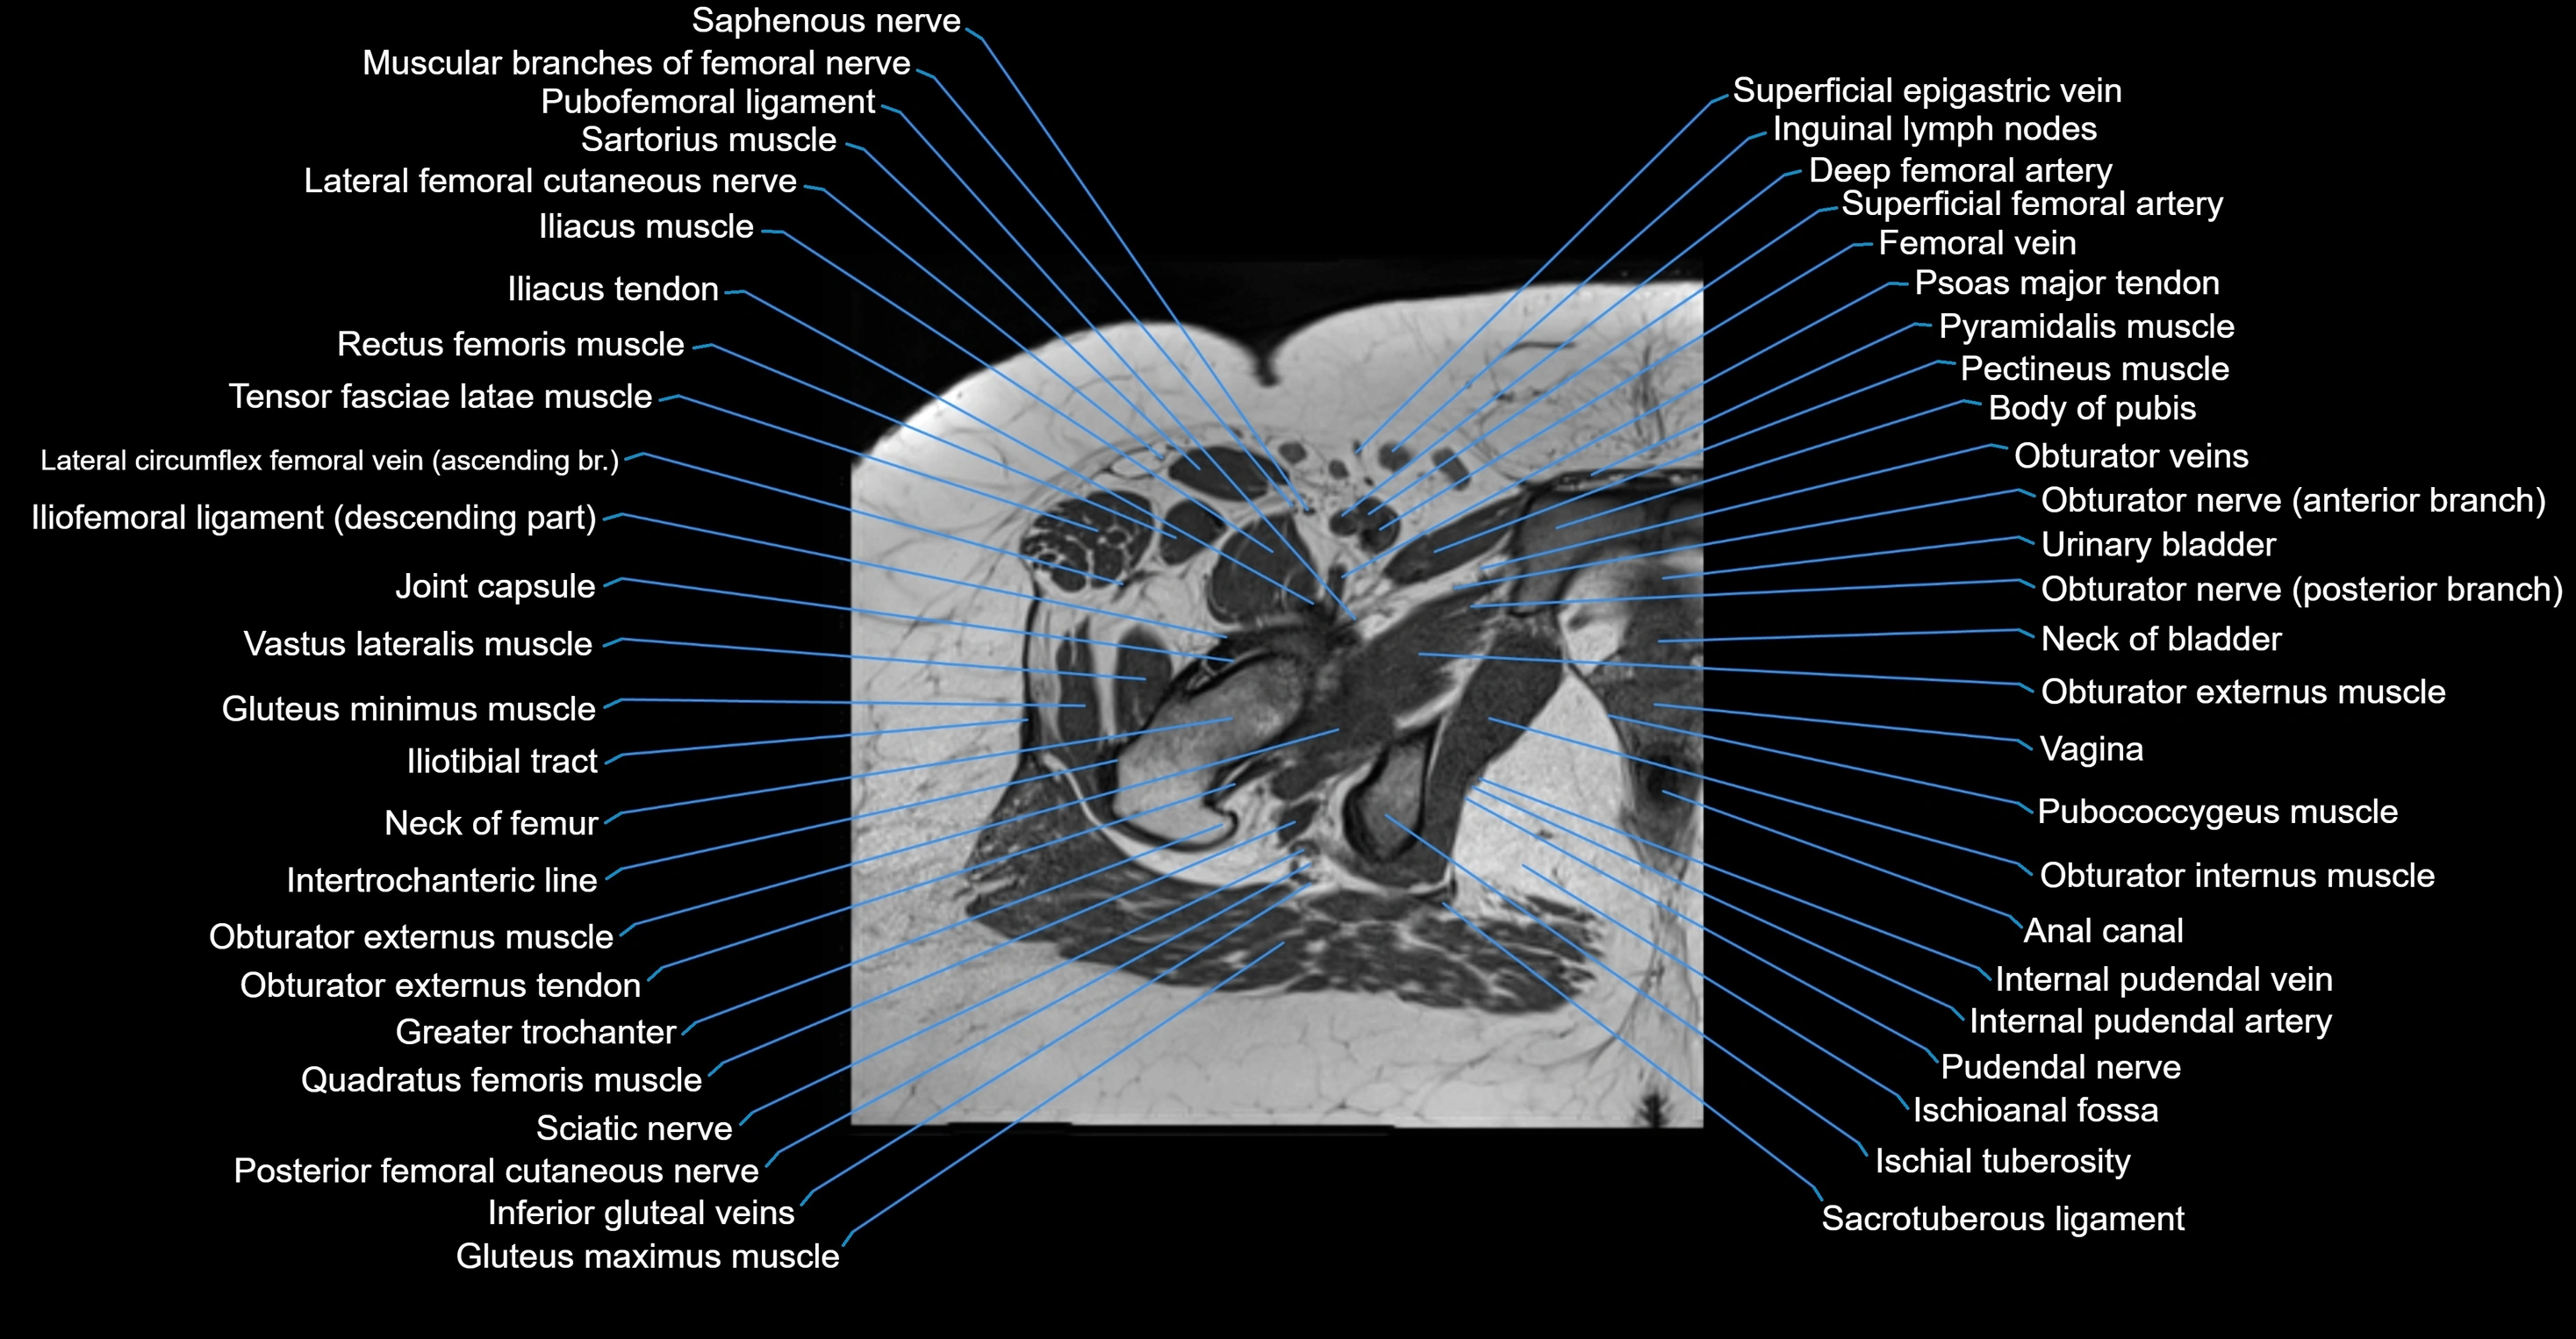

- Anal canal

- Body of pubis

- Body of urinary bladder

- Gluteus medius muscle

- Gluteus minimus muscle

- Greater trochanter

- Iliotibial tract

- Inguinal lymph nodes

- Intertrochanteric line

- Ischial tuberosity

- Ischioanal fossa

- Neck of femur

- Obturator externus muscle

- Obturator externus tendon

- Obturator internus muscle

- Psoas major muscle

- Pubococcygeus muscle

- Pudendal nerve

- Pyramidal muscle (pyramidalis muscle)

- Quadratus femoris muscle

- Sartorius muscle

- Tensor fasciae latae muscle

- Urinary bladder

- Vagina

- Vastus lateralis muscle